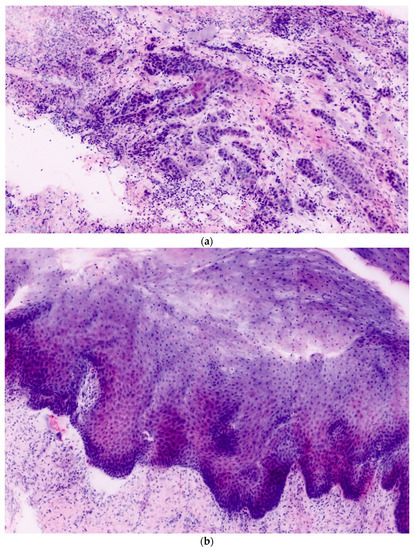

In total, 106 ex vivo images of 27 oral lesions from the 22 patients enrolled in the study were obtained. For each FCM lesion, corresponding H&E histopathology was completed. Each confocal mosaic image was divided into four submosaics and displayed with an approximate magnification of 550×. An example is presented in Figure 1a,b. From 27 mosaics, 106 submosaics were created: 54 (51%) contained leukoplakia and 52 (49%) did not.

Figure 1. (a,b) Examples of ex vivo confocal microscopy mosaics of leukoplakia.